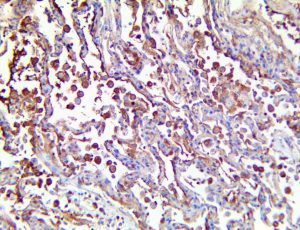

It is the ICU physician who is most likely to witness one of the deadliest manifestations of the abnormal immunological response, the cytokine storm syndrome (CSS). This response is also referred to by some as the cytokine release syndrome (CRS). CSS is characterized by continuous activation and expansion of macrophage and lymphocyte populations, which secrete large amounts of cytokines, causing the cytokine storm. This massive cytokine release is akin to hemophagocytic lymphohistiocytosis (HLH) disease, a syndrome characterized by initial unchecked and persistent activation of cytotoxic T lymphocytes and NK cells.

Clinical and laboratory manifestations of HLH include fever, enlarged liver and/or spleen, neurologic dysfunction, coagulopathy, liver dysfunction, cytopenias (i.e., low levels of erythrocytes, leukocytes, and/or platelets), hypertriglyceridemia, hyperferritinemia, hemophagocytosis, and eventually diminished NK cell activity as the immune system becomes progressively paralyzed. HLH can be familial (primary HLH) or secondary to another disease process (sHLH), such as rheumatic disease, in which it is referred to as macrophage activation syndrome (MAS, characterized by elevated ferritin).